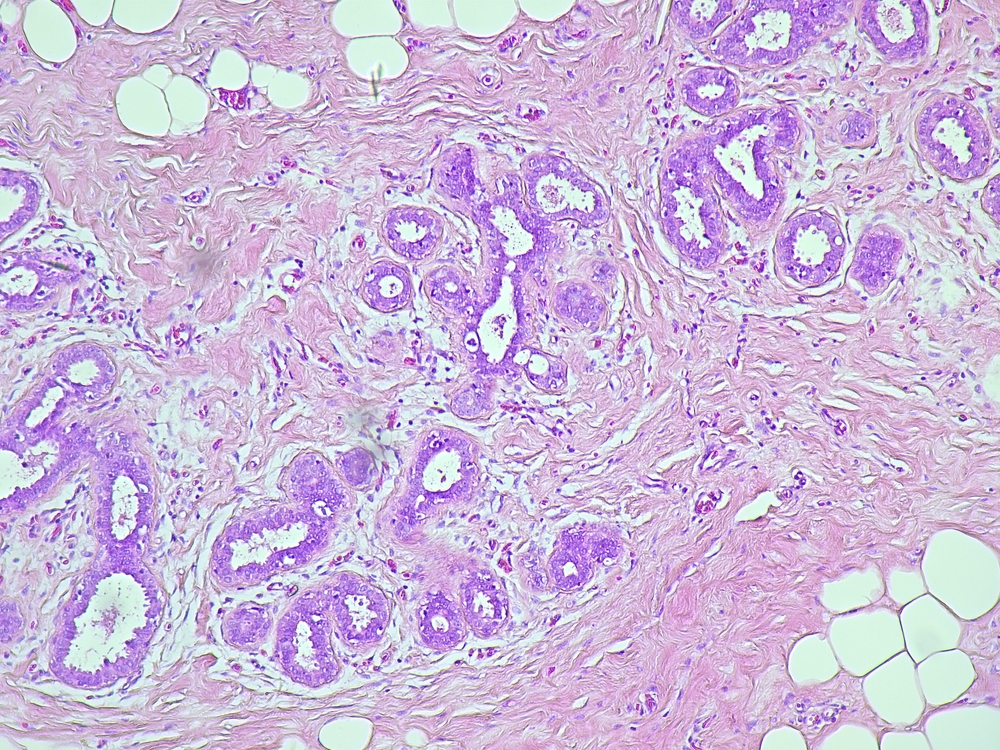

One of our areas of focus is the diagnosis of breast diseases. We specialize in the evaluation of breast biopsies and surgical specimens and offer comprehensive morphological and immunohistochemical characterization of preinvasive lesions and breast carcinomas (including predictive markers such as ER, PR, HER2, and Ki67). Findings are reported in accordance with guidelines to serve as the basis for surgical and systemic treatment plans. For quality assurance, we place great emphasis on second opinions for biopsies. Close interdisciplinary collaboration with clinical colleagues is of particular importance to ensure a high degree of reliability and quality in our findings. Our institute is a certified partner of several breast centers.